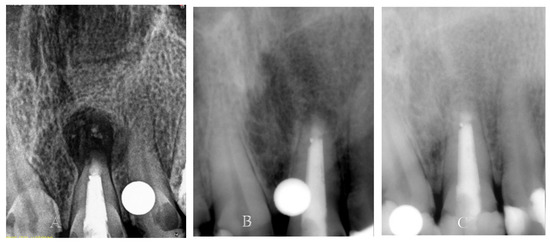

Figure 5.

(A). Immediate postoperative periapical radiograph showing periapical radiolucency around the apex of Tooth 12. (B). Periapical radiolucency decreased in six months. (C). Complete resolution of periapical radiolucency in one year.